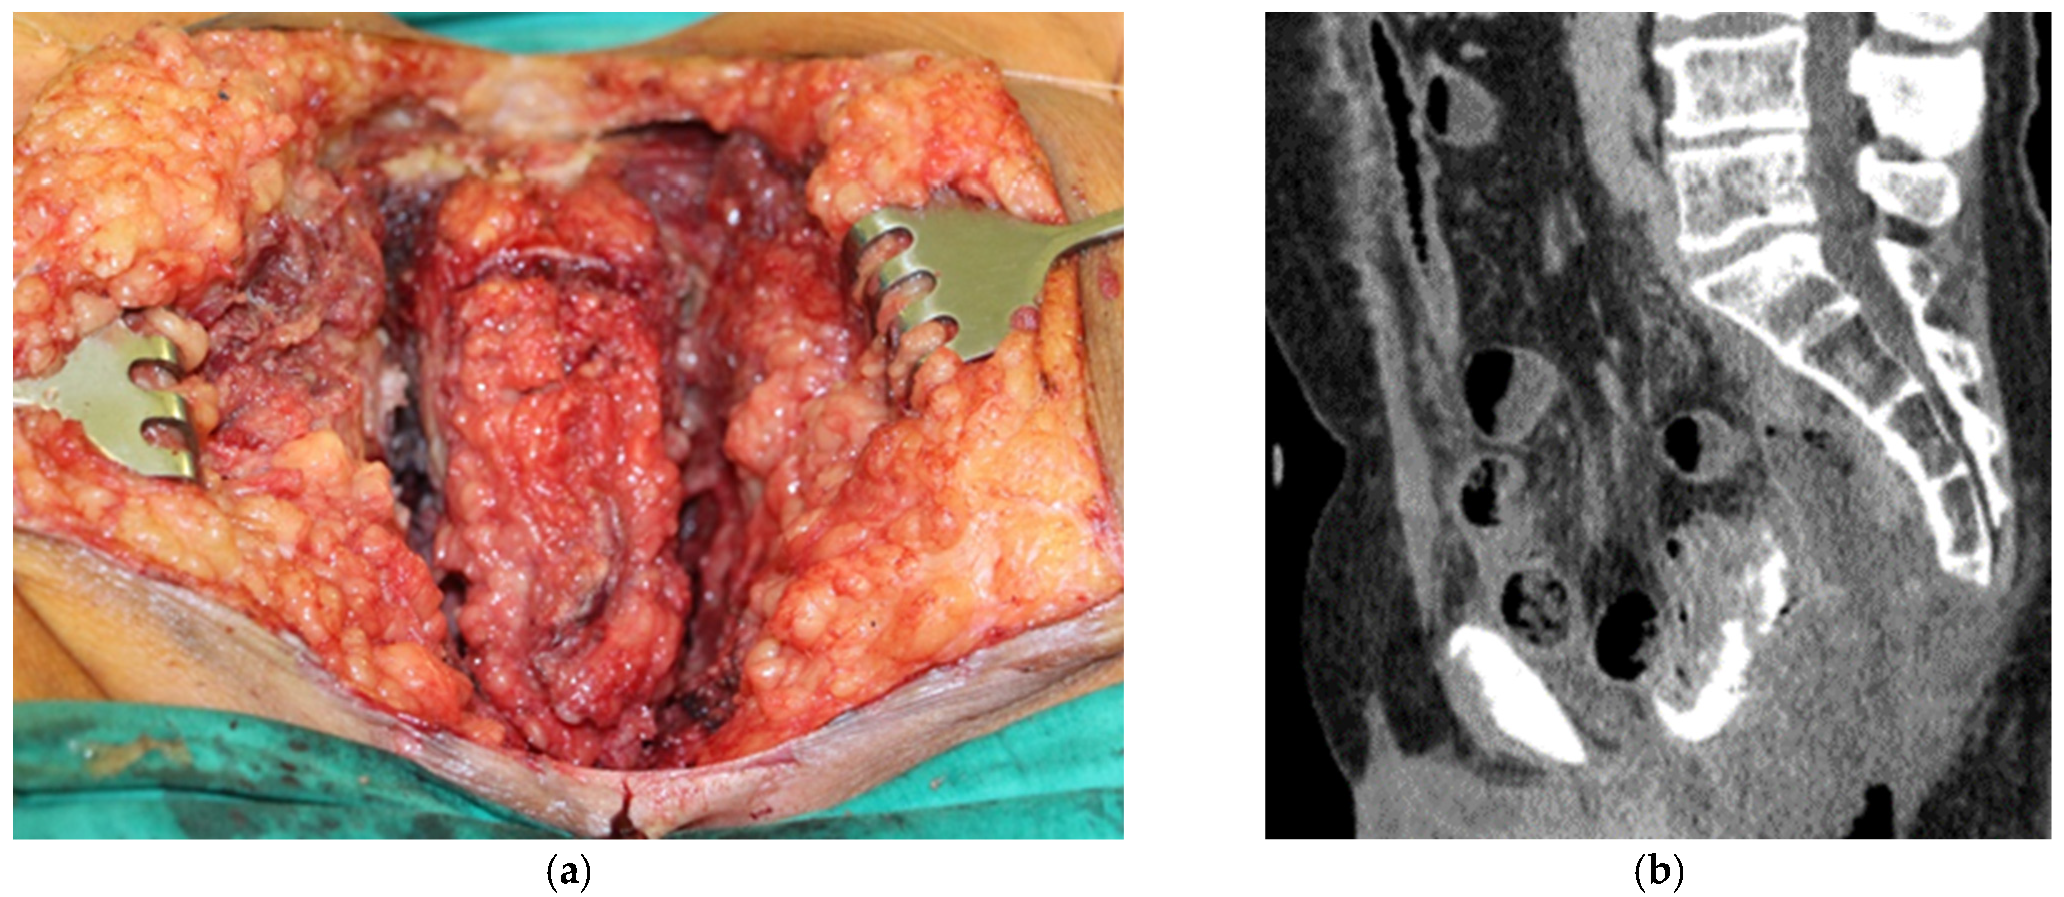

| 3 | Ovarian cancer T3cNxM1 IVa st.1 | Combined cytoreductive (initially optimal) operation: posterior supralevator evisceration of the small pelvis. Resection of the right dome of the diaphragm. Resection of the greater and lesser omentum. Obstructive resection of the sigmoid colon. Total peritonectomy. Cholecystectomy, splenectomy, appendectomy. Resection of the right ureter (Figure 8). | 390 |